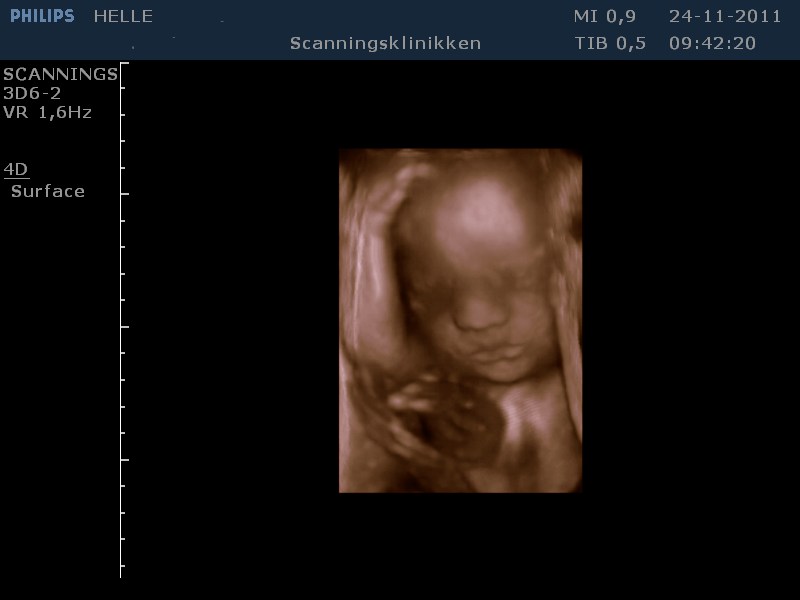

Her går det også godt, - er lige kommet hjem fra en fantastisk 3D scanning. Vores lille pige har det godt og er helt igennem fin! SÅ SØD! Hun har indhentet den manglende vægt og ligger nu lige over gennemsnittet med ca. 1500 g, så det er dejligt!